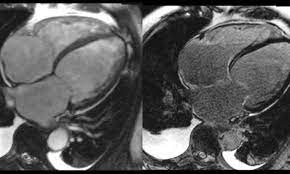

Breitenseher Publisher Herzbildgebung

Breitenseher Publisher Herzbildgebung from breitenseher.eu

Bei der ödemdarstellung am herzen.